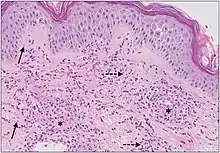

Micrograph of cutaneous small-vessel vasculitis. The section shows all features of leucocytoclastic vasculitis. A mixed inflammatory cell population surrounding the postcapillary venules of the superficial dermis. The infiltrate consists of neutrophils with nuclear dust (dashed arrows) and shows high affinity for the vessels. Features of vascular injury are shown including fibrinoid necrosis (asterisks) and erythrocyte extravasation (solid arrows).[11]

The small vessels in the skin affected are located in the superficial dermis and include arterioles (small arteries carrying blood to capillaries), capillaries, and venules (small veins receiving blood from capillaries).[5] In general, immune complexes deposit in vessel walls leading to activation of the complement system. C3a and C5a, proteins produced from the complement system, attract neutrophils to the vessels.[9] Once activated, neutrophils then release preformed substances, including enzymes causing damage to vessel tissue.[9] Evidence of this process can be seen with a sample of removed skin tissue, or biopsy, viewed under a microscope. Neutrophils are seen surrounding blood vessels and their debris within vessel walls, causing fibrinoid necrosis. This finding on histological examination is termed "leukocytoclastic vasculitis".[5]